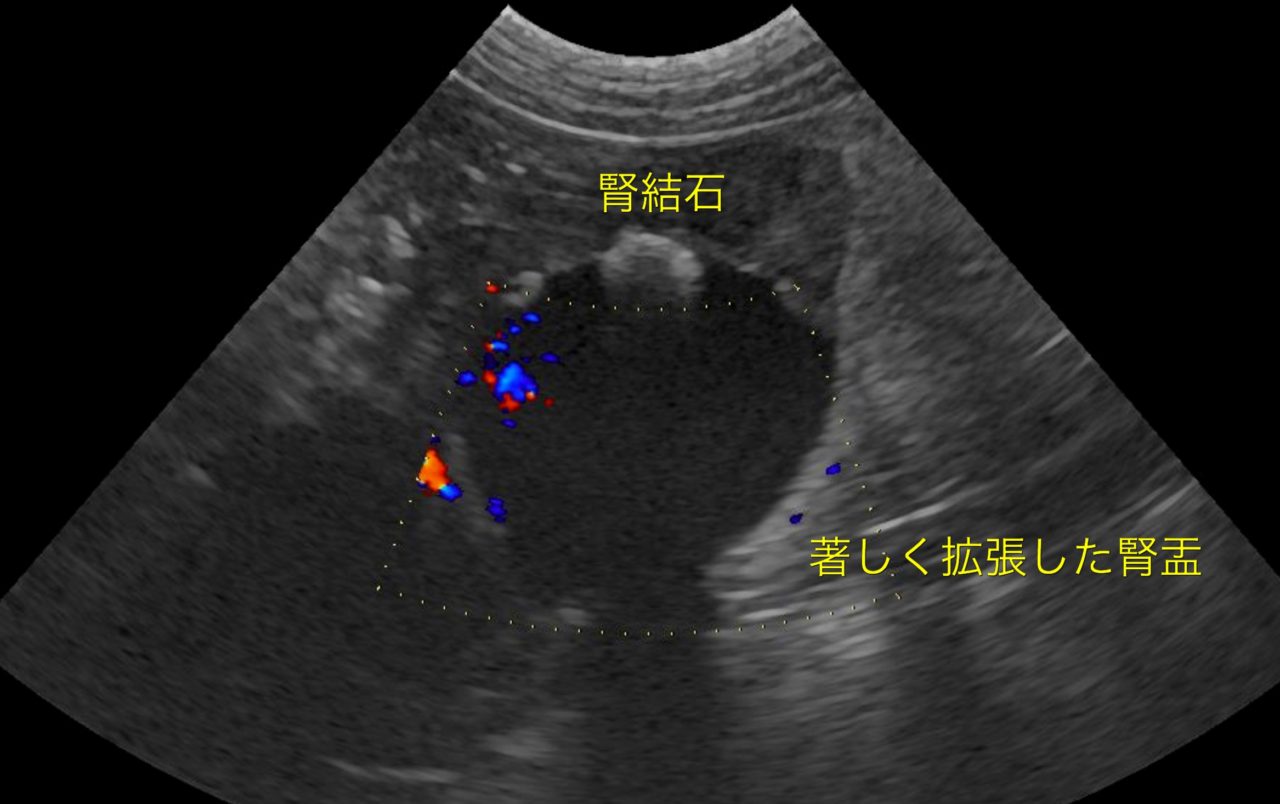

かかりつけ医で定期的に超音波検査で腎結石のモニターをしていたところ、急に腎盂が拡張してきたので早急に対応して欲しいと連絡がありました。尿管結石により尿路閉塞が起こっていました。マイクロサージェリーで尿管を2箇所切開し、尿管結石を摘除しました。術後の狭窄予防に一時的に尿管ステントを留置しています。術後翌日から、腎盂拡張は解消しましたが、術後の経過により、生体にとって異物となる尿管ステントは抜去する予定です。